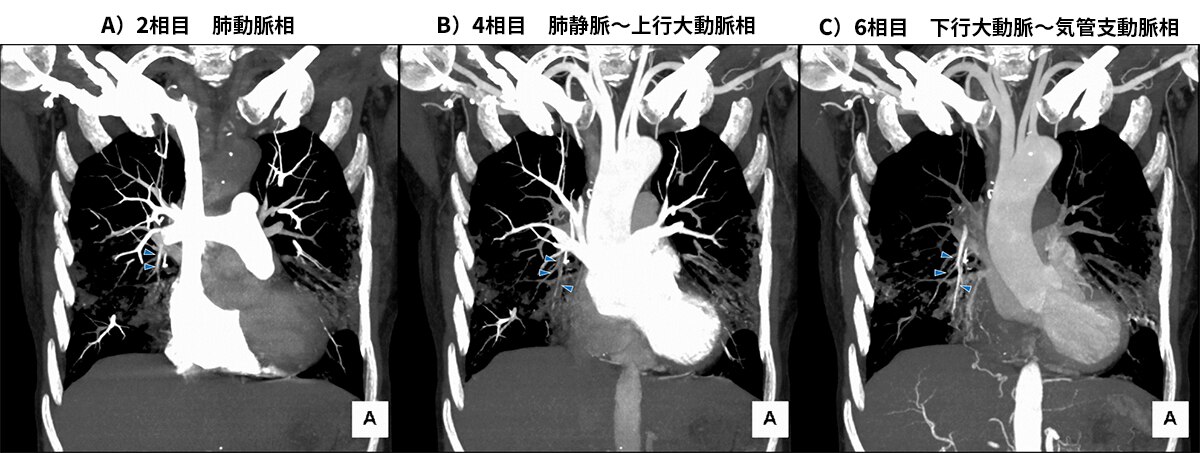

図3 冠状断のMIP再構成画像

A)の肺動脈相で他の肺動脈よりは弱い造影効果をもつ肺動脈右A5(►)がB)の肺静脈相では造影効果が消失し、C)の下行大動脈相では他の肺動脈と異なり肺動脈右A5に強い造影効果を認める。これは気管支動脈(もしくは他胸郭周囲の体循環系動脈)とのシャント血流があるため、肺動脈相では体循環系からの逆流で他の肺動脈に比べ造影効果がやや低下し、大動脈相で気管支動脈からシャントを経て造影剤が肺動脈に逆流するためである。